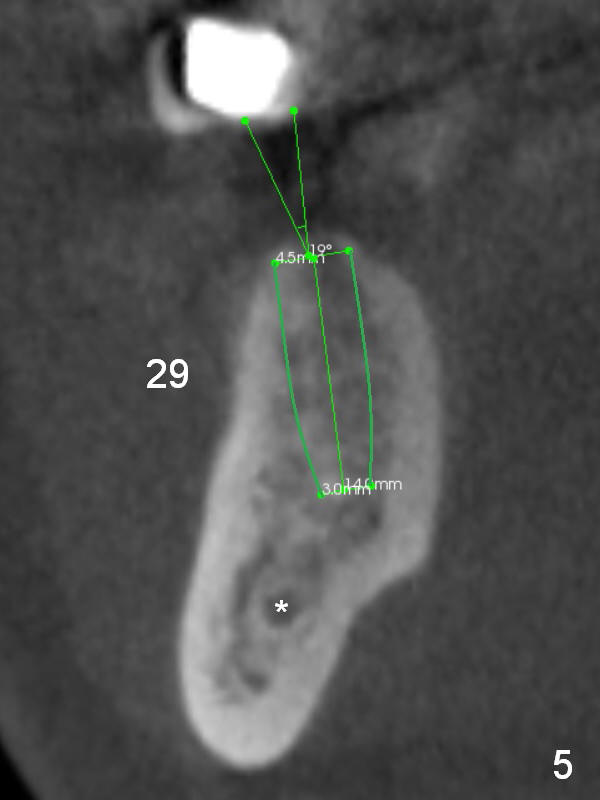

In contrast, the edentulous ridge at the site of #29 is not narrow (Fig.5). A longer implant can be placed (14 mm vs. 12 mm for #28). The patterns of bone resorption at the lower left premolars are quite similar or worse.